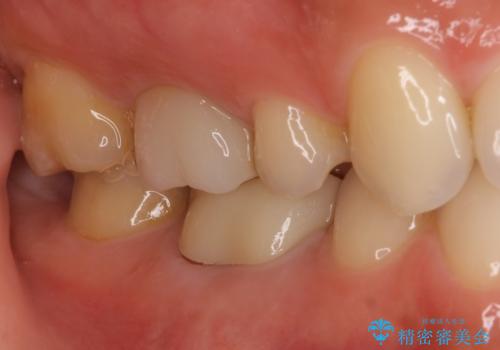

根管治療を行った奥歯は、再発防止や残された歯質を守るため、クラウンによる補綴治療が必要となります。

補綴後6か月経過しレントゲンを撮影したところ、根尖周辺の病変が消失していることが確認できました。